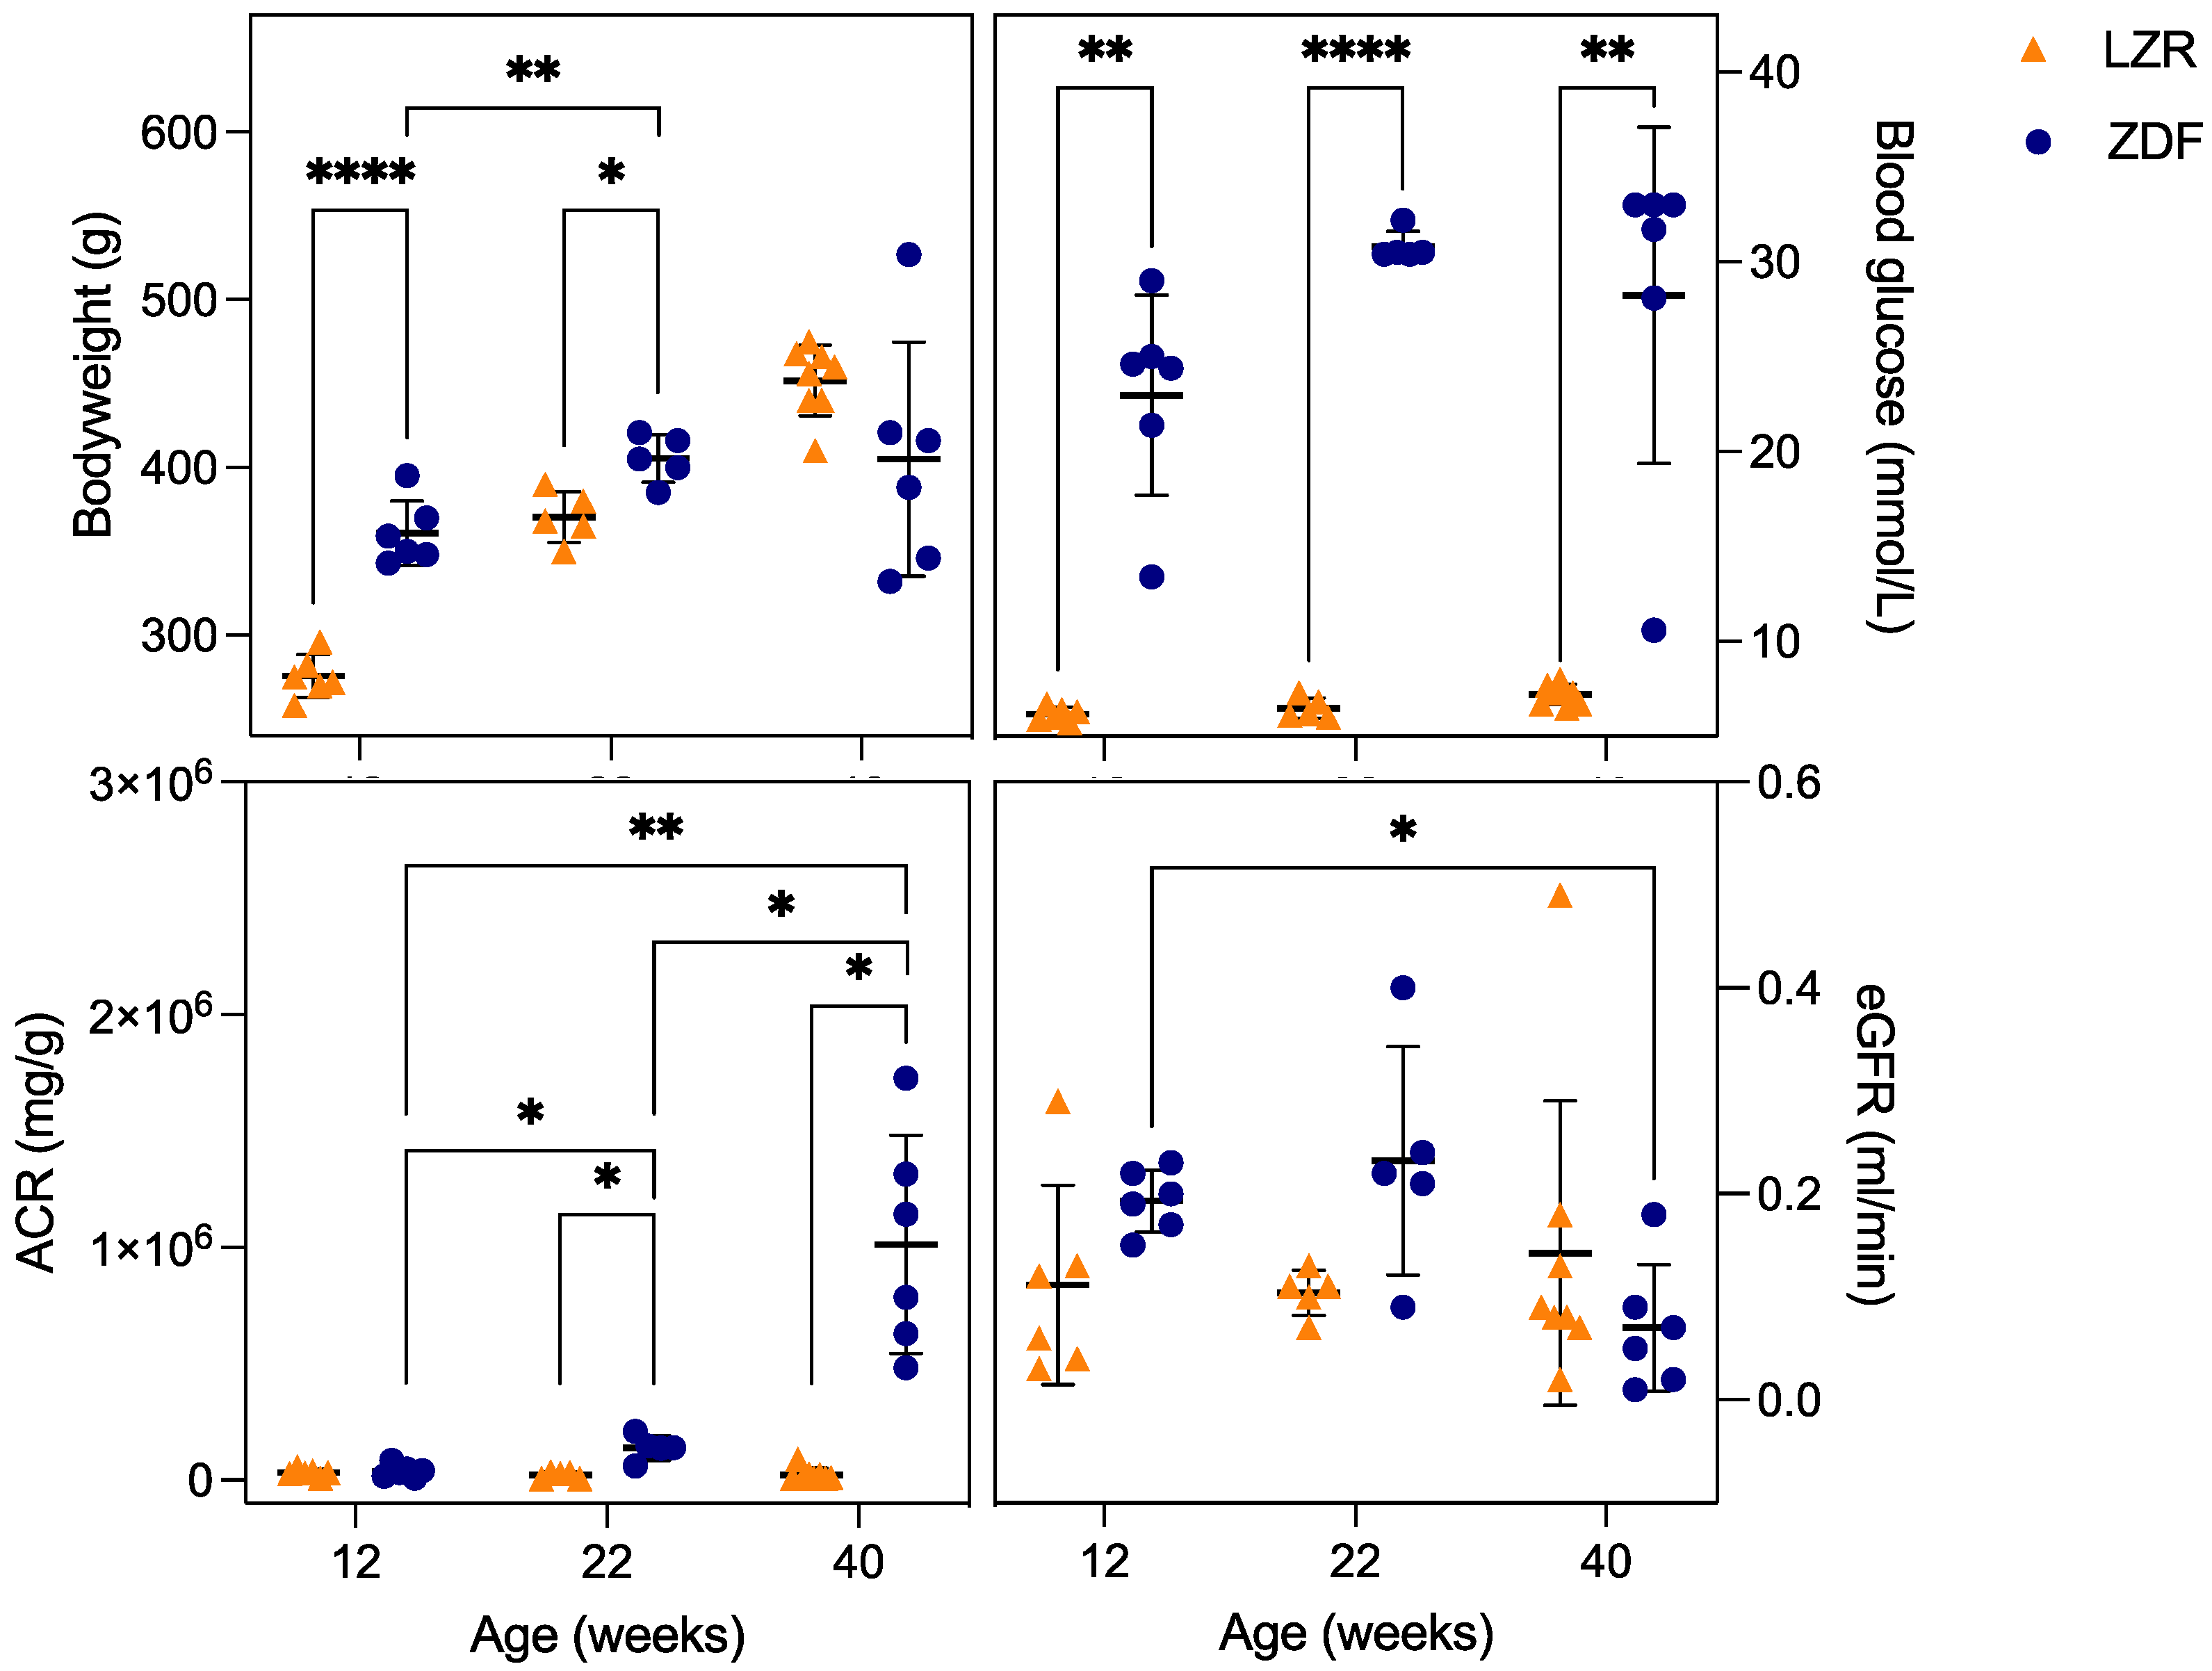

3.1. Metabolic Parameters

- Baynes, J.; Murray, D.B. Cardiac and Renal Function Are Progressively Impaired with Aging in Zucker Diabetic Fatty Type II Diabetic Rats. Oxidative Med. Cell. Longev. 2009, 2, 328–334. [Google Scholar] [CrossRef]

- Silveiro, S.P.; Friedman, R.; Gross, J.L. Glomerular Hyperfiltration in NIDDM Patients without Overt Proteinuria. Diabetes Care 1993, 16, 115–119. [Google Scholar] [CrossRef]

- Tonneijck, L.; Muskiet, M.H.A.; Smits, M.M.; Van Bommel, E.J.; Heerspink, H.J.L.; Van Raalte, D.H.; Joles, J.A. Glomerular Hyperfiltration in Diabetes: Mechanisms, Clinical Significance, and Treatment. J. Am. Soc. Nephrol. 2017, 28, 1023–1039. [Google Scholar] [CrossRef]

- Habib, S.L. Kidney Atrophy vs Hypertrophy in Diabetes: Which Cells Are Involved? Cell Cycle 2018, 17, 1683–1687. [Google Scholar] [CrossRef]

- Rave, K.; Nosek, L.; Posner, J.; Heise, T.; Roggen, K.; Hoogdalem, E.-J. van Renal Glucose Excretion as a Function of Blood Glucose Concentration in Subjects with Type 2 Diabetes—Results of a Hyperglycaemic Glucose Clamp Study. Nephrol. Dial. Transplant. 2006, 21, 2166–2171. [Google Scholar] [CrossRef] [PubMed]

- Vora, J.P.; Zimsen, S.M.; Houghton, D.C.; Anderson, S.; Vora, J.P.; Zimsen, S.M.; Anderson, S.; Houghton, D.C. Evolution of Metabolic and Renal Changes in the ZDF/Drt-Fa Rat Model of Type II Diabetes. J. Am. Soc. Nephrol. 1996, 7, 113–117. [Google Scholar] [CrossRef]